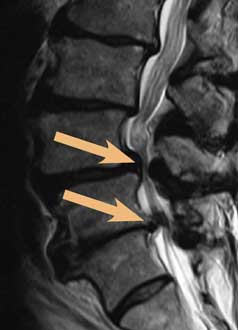

Die Abbildung zeigt eine hochgradige Spinalstenose, die in zwei Höhen auf die Nervenwurzeln drückt (Nervenwurzelkompression).

Um die Spinalstenose von anderen Erkrankungen abzugrenzen, die ähnliche Beschwerden verursachen, werden Patienten zunächst neurologisch-orthopädisch untersucht inklusive einer umfangreichen Anamneseerhebung. Im Anschluss daran werden häufig bildgebende Untersuchungen wie die MRT durchgeführt. Mit der Magnetresonanztomographie lassen sich Spinalkanalstenose und andere Erkrankungen der Wirbelsäule sehr gut untersuchen und sichtbar machen.

In der Beta Klinik verwenden wir einen offenen MRT, der es uns bei der Diagnostik der Spinalstenose der Lendenwirbelsäule ermöglicht, auch klaustrophobische Patienten oder solche bis 250 kg komfortabel zu untersuchen.